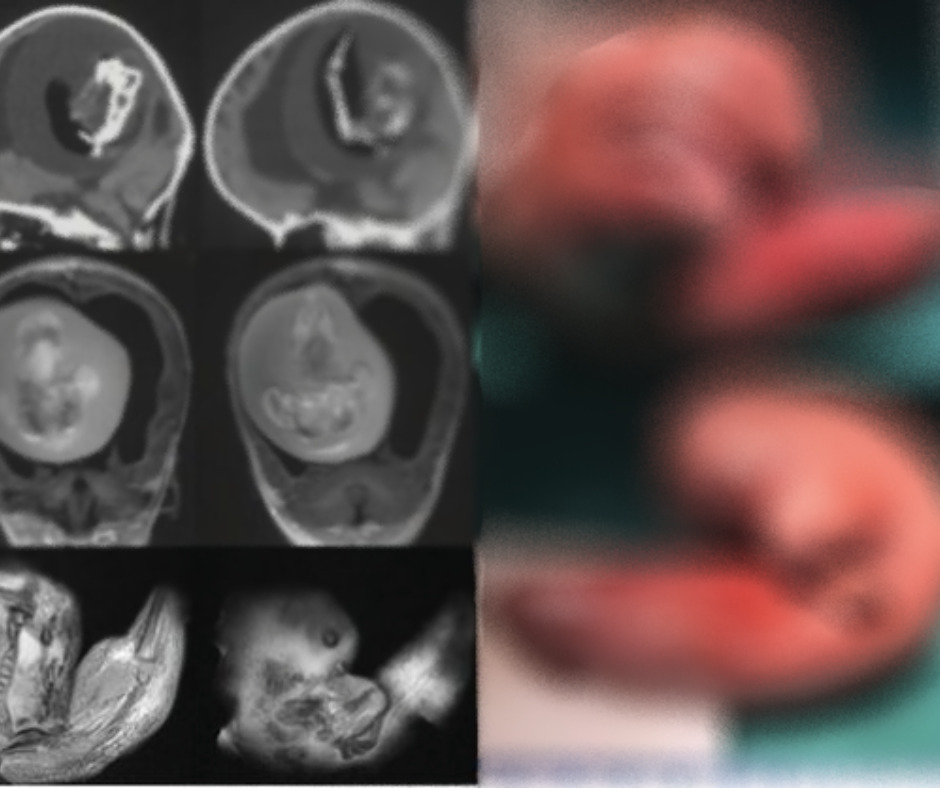

CHINA (CN) – Uma menina de 1 ano precisou ser submetida a uma cirurgia para retirar o feto da irmã gêmea idêntica de dentro do próprio cérebro; o feto tinha cerca de 10 cm.

De acordo com os médicos do hospital universitário da Universidade de Fudan, na China, a gêmea não nascida desenvolveu membros superiores, ossos e unhas após passar um ano parasitando e se nutrindo do sangue dela. A condição é conhecida como feto no feto.

“O feto no feto intracraniano surge de blastocistos [um dos estágios do desenvolvimento de um embrião] não separados. As partes unidas se desenvolvem no prosencéfalo [parte anterior da vesícula cerebral] do feto hospedeiro e envolvem o outro embrião durante o dobramento da placa neural [começa a partir do 22º dia de gestação]”, explicou Zongze Li, neurologista que tratou a menina, ao site de notícias britânico Daily Star.

O caso foi descoberto após os pais da criança levarem ela ao médico devido ao crescimento incomum da cabeça, e também por algumas habilidades motoras estarem comprometidas.

A filha do casal tinha hidrocefalia, o que já acumulava uma grande quantidade de líquido no cérebro.

Mas por meio da tomografia foi descoberto que havia um feto vivendo na cabeça da garota. A gêmea foi removida por meio de cirurgia, e ainda não é possível dizer se a menina terá danos a longo prazo.

Segundo o Dayli Star, a condição é extremamente rara e foi encontrada apenas 200 vezes, sendo 18 delas no cérebro – também pode ocorrer na pelve, boca, intestino e escroto.

Foto: Reprodução / Neurology